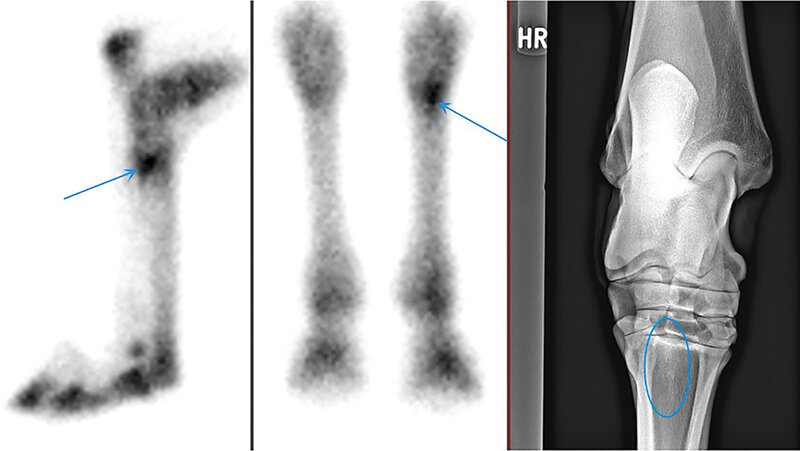

Eine ältere Vollblutstute wurde mit akuter, hochgradiger Hinterhandlahmheit und Schwellung zur weiteren bildgebenden Diagnostik sowie Therapie vorgestellt. Die klinische, röntgenologische sowie sonografische Untersuchung folgerte in einem Fissurverdacht im Beckenbereich und das Pferd durchlief daraufhin eine Knochenszintigrafie zur Abklärung. Der Verdachtsbefund erhärtete sich und das Pferd wurde für etwa einen Monat im Schwinglifter entlastend ruhiggestellt, bis es nach Hause entlassen wurde. Hier verschlechterte sich der Zustand rapide und zog schließlich die Euthanasie nach sich.

An older thoroughbred mare was presented with an acute, severe hind limb lameness and swelling for further imaging diagnostics and therapy. Clinical, radiographic and sonographic examinations revealed a suspected fissure in the pelvic region and the horse underwent a bone scintigraphy for clarification. The suspicious findings were confirmed and the horse was immobilised for about 1 month in a swinglifter until it was discharged home. Here the condition deteriorated rapidly and finally resulted in the horse’s euthanasia.